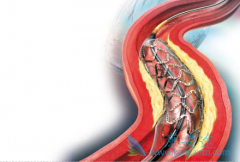

心脏支架作为现代心血管医学发展中的一个里程碑,确实在冠心病的治疗中发挥着非常重要的价值。 生物可降解支架 给冠心病介入治疗带来了新的革命。但是生物可降解支架真的能成为心血管患者的福音吗?目前心脏支架主要分为不可降解支架和完全降解支架两个 ...

生物可降解支架 安全吗?其实早在20世纪90年代初,就已经提出生物可降解支架的概念,但发展没有金属裸支架和药物洗脱支架快,最终被药物洗脱支架所替代。目前药物洗脱支架长期随访发现潜在的支架内血栓风险,最近10余年生物可降解支架科技和材料学取得 ...

为了改善冠心病介入治疗短期和长期的疗效与安全性,所以研发了支架。第一代支架是金属裸支架,使冠心病介入治疗前进了一大步,使介入治疗变得非常安全,当血管发生严重狭窄时单纯球囊扩张预处理后,再用支架把血管完全撑开,就能解除心肌缺血危险,而且 ...

心脏支架 选哪种?放最好的支架?还是放最贵的支架?今天就给大家答疑解惑!心脏支架由具有强支撑力的合金制成,不同厂家支架的金属结构略有差别。心脏支架没有植入体内之前,包裹在球囊外面。植入时给球囊加压,支架打开至预定直径,使支架与血管壁完 ...